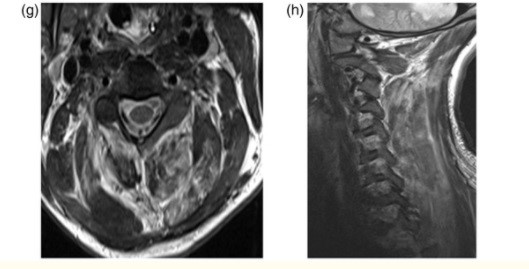

Asimismo, la adicción a la heroína también genera afectaciones a nivel del SNC, provocando secuelas neurovasculares agudas y crónicas, como leucoencefalopatías, atrofia e infección. Las complicaciones agudas, como los ACV o la isquemia, suceden generalmente con la administración intravenosa de esta sustancia, que produce vasoespasmo, vasculitis y eventos embólicos.(22, 24) Se puede mencionar el caso de una mujer de 48 años con antecedentes de abuso de heroína, quien sufrió infarto agudo de divisoria de aguas con afectación de los lóbulos frontales y el justo caudal(24) (ver Imagen 17).

Entre el 5% y el 10% de las personas que tienen infartos asociados a la heroína se involucran globus pallidus o los ganglios basales. De igual forma, con la adicción a esta sustancia ocurren cambios isquémicos crónicos, a menudo son subclínicos, que se desarrollan a partir de estructuras microvasculares a largo plazo(24) (ver Imagen 18).

La endocarditis provoca infartos en el SNC debido a la oclusión de émbolos sépticos, aneurismas micóticos y en menor medida abscesos cerebrales(22) (ver Imagen 19). La heroína también provoca atrofias severas a nivel cerebral, como surcos y espacios subaracnoideos en los lóbulos frontal y temporal (ver Imagen 20).